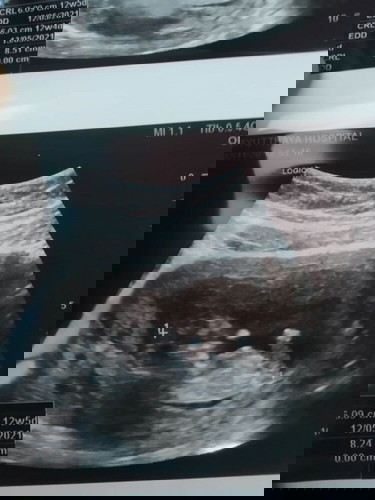

ตอนนี้ท้องได้12สัปดาห์ เเล้วไปซาวด์มาหมอบอกลูกมีขนาด8.5เซน เเบบนี้ถือว่าขนาดปกติหรือเล็กไปคะ กลัวน้องออกมาตัวเล็ก ท้องเเรกค่ะไม่รู้เรื่องอะไรสักเท่าไหร่ ช่วยบอกหน่อยนะคะ

ลองเทียบขนาดที่ได้มา กับแอปนี้ดูนะคะ มีบอกไว้ค่ะ